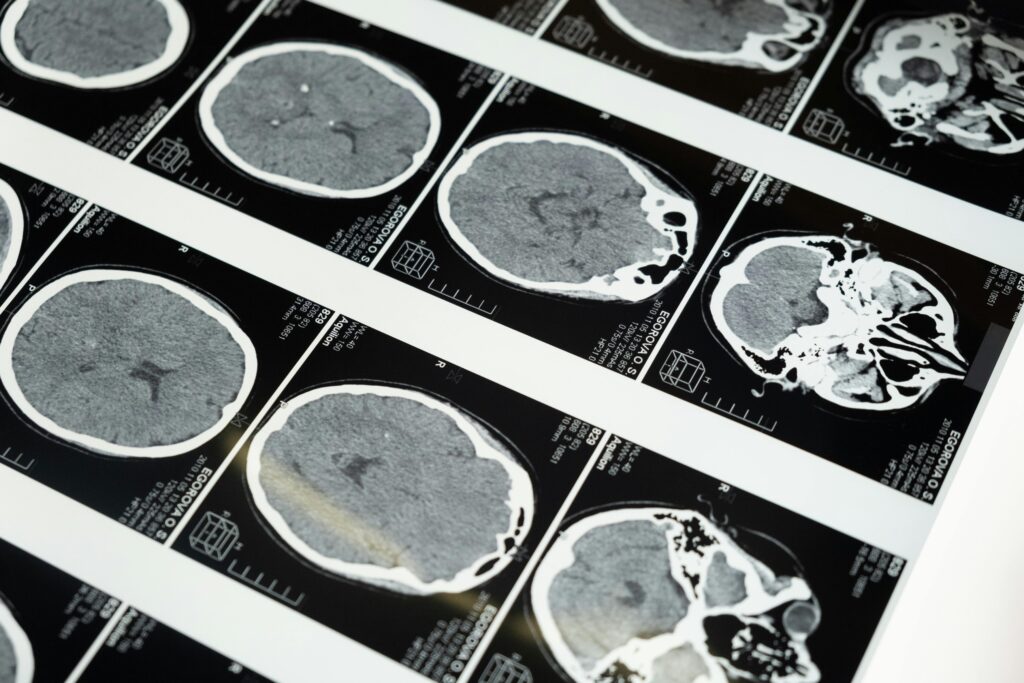

Diagnosis of a brain tumour

Imaging plays a central role in diagnosis. Magnetic resonance imaging (MRI) is the most commonly used technique, providing detailed images of the brain to identify the presence, size and location of a tumour. CT scans may also be used, particularly in emergency settings.